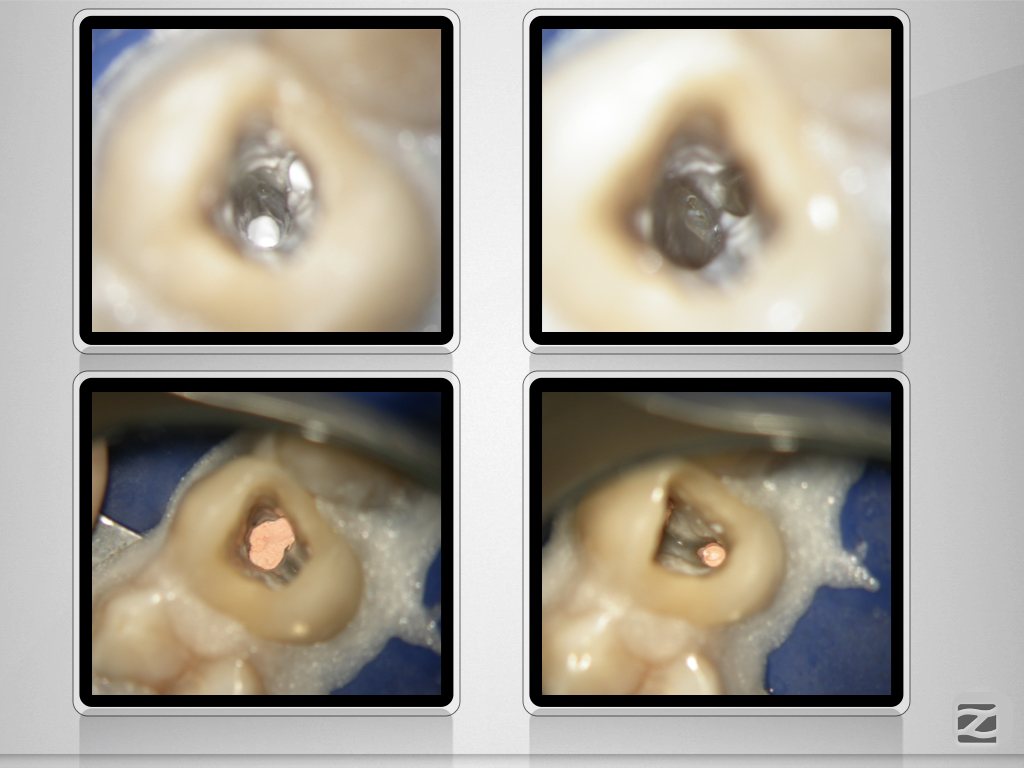

24D.007

Enger Dreier